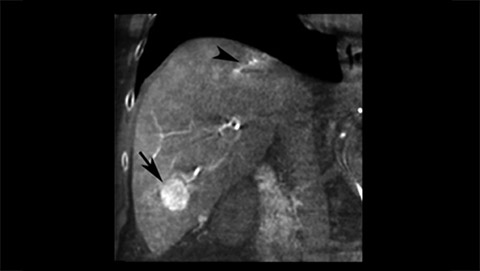

XperCT extends the capabilities of the interventional suite offering CT like imaging to visualize bone, soft tissue and vessels in case of contrast enhanced acquisition. XperCT supports fast abdominal protocols with 5 to 8 seconds acquisition time for excellent image quality while significantly minimizing respiratory artifacts. The XperCT 3D volume is displayed automatically within 8 to 15 seconds after the acquisition and confirms selective targeting of hepatic lesion and helps avoid untargeted embolization and drug delivery.